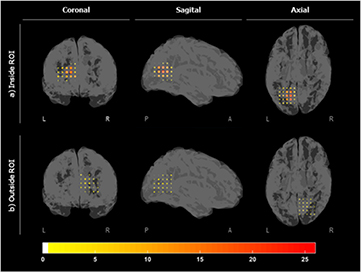

The localization maps inside and outside the ROI for patient 1 are shown in figure 7. These maps measure the number of times that a specific virtual sensor was associated to a ripple. Figure 8 shows the grid inside and outside in slices (of the z-plane) for the nine subjects. These figures suggest that specific VSs appeared clustered, close to each other and involved in a high number of ripples inside the ROI, showing a more focalized localization map than outside the ROI. In order to quantify this effect, the percentage of detected ripples for the most active region inside and outside the ROI is shown in table 4. To compute this score, the VS showing the highest number of ripples and its six closest neighbors were selected for each subject. The ratio of the average number of ripples detected in seven clustered VSs to the number of detected ripples was then computed. As expected, the percentage of ripples involved in the most active region inside the ROI was significantly higher (p-value < 0.001) than outside the ROI.

Figure 7. Localization maps for the number of detected ripples (a) inside the ROI and (b) outside the ROI, on the contralateral hemisphere for patient 1.

Standard image High-resolution imageFigure 8. Localization maps in slices of the number of detected ripples for all subjects for (a) inside the ROI and (b) outside the ROI. The colormap measures the number of times that a VS appeared in a ripple.

3.4. Detection and localization of ripples inside and outside the ROI

The average number of detected ripples inside the ROI was 31.8 ± 13.2 and this value decreased to 13.4 ± 5.0 when computed outside the ROI (mean ± SD). The number of VSWS involved in each ripple event was also computed. An average number of 18.4 ± 4.0 VSs were involved in each ripple event inside the ROI, whereas this value was slightly lower outside the ROI which showed an average of 12.6 ± 3.8 VS. The differences (inside and outside the ROI) between the number of detected ripples and the average number of VSs were statically significant (paired t-tests, significance set to 0.05) with probability values of 0.002 and 0.02, respectively. Table 4 shows the number of detected ripples outside the ROI and the mean number of VSs involved in each ripple for each patient.

An automatic selection of the area that showed the highest number of EOIs was performed to circumscribe the detection of ripples to a volume of approximately 9 cm3. This area agreed with the zone targeted by clinicians (tables 1 and 2). The HFO detection algorithm was applied to the same volume in the contralateral hemisphere with the purpose of comparing the number of ripples and the pattern drawn by VSWS involved (figures 6 and 7). In general, a group of VSs that were detected simultaneously in different ripples produced a focalized map inside the ROI. Although this information was still insufficient to provide a reliable localization of the area generating pathological HFOs because of the lack of precise clinical information, it could be inferred that the oscillations were mostly generated by a common focus and this provides a general idea of the area where the ripples appeared. It is important to remark that although the automatic detection algorithm uses an ROI to detect ripples, these can be mapped a posteriori throughout the head by using temporal information about the detected ripple segments.

The proposed algorithm also detected some ripples outside the ROI, but the number of events was significantly lower and involved fewer VS. There is still uncertainty between the differential characteristics and mechanisms of pathological and physiological ripples [48]. Whether all the detected events were actually physiological, pathological or noise cannot be demonstrated definitely, but the detected ripples outside the ROI presented lower values of energy, which is a characteristic of physiological HFOs [49]. Moreover, the pattern of these oscillations appeared to be more scattered throughout the volume, indicating that these oscillations were not generated by a common area or focus. This finding is in correspondence to observations with animal studies indicating that the areas generating physiological HFOs appeared more extended [50] than the areas generating pathological HFOs, which are smaller brain regions on the order of cubic millimeters [51]. The results from Zelmann et al [18] suggested that it is possible to measure the activity from small cortical regions at scalp level. This could be explained by the solid angled concept introduced by Gloor [52]. These measurements should be comparable with those obtained with subdural grid contacts, always taking into account that the spatial resolution of the technique should be high.